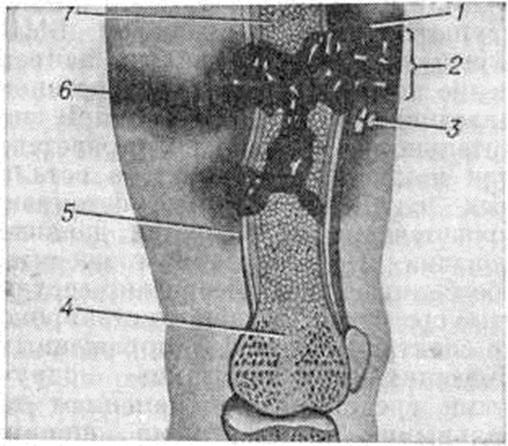

При патологический Переломы длинных трубчатых костей нижней конечности нередко применяют внутрикостный остеосинтез длинным металлическим гвоздём. При этом не преследуют цель устранения метастазов или создание условий для сращения патологический Переломы Таким образом на какой-то период фиксируют отломки и создают «внутренний протез» кости. Больной получает возможность в течение некоторого времени передвигаться с помощью костылей, и это создаёт иллюзию улучшения. При первичных злокачественных опухолях и в ряде случаев при солитарном метастазе после удаления первичной опухоли по поводу патологический Переломы производят ампутацию (смотри полный свод знаний) или экзартикуляцию (смотри полный свод знаний) конечности. При патологический Переломы на почве некоторых медленно развивающихся злокачественных опухолей, а также при доброкачественных опухолях применяют сберегательные операции, направленные на сохранение конечности. Производят частичную или полную резекцию очага поражения без костной пластики или с костной аллопластикой, остеосинтез различными конструкциями, эндопротезирование (смотри полный свод знаний).

Действие огнестрельного снаряда на живые ткани слагается из силы прямого удара, воздействующего на ткани участка, где пуля или осколок непосредственно соприкасаются с ними, и силы бокового удара, возникающего за пределами раневого канала в тканях, расположенных на различном расстоянии от места прохождения ранящего снаряда (рисунок 14). При многооскольчатых Переломы костные осколки играют роль вторичных снарядов и вызывают значительные разрушения мягких тканей. Наличие большого количества некротических тканей по ходу раневого канала и в окружающей зоне создаёт благоприятную среду для развития гнойных осложнений.